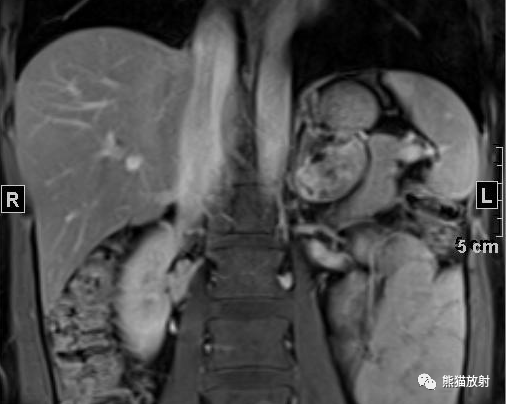

女性,47岁,阵发性头晕、视物模糊4年余,查体发现肾上腺占位。

行肾上腺MRI平扫+增强扫描

⭐️ 左侧肾上腺皮质腺瘤,合并髓样脂肪瘤

? 病灶内含成熟脂肪和脂质成份,在T1反相位和压脂像上局部信号减低。